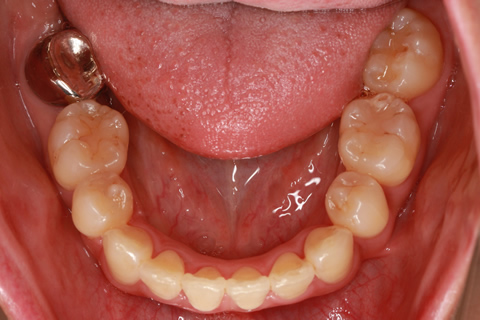

フルリンガル矯正2:上下の歯を舌側矯正で治療(矯正期間18ヶ月)

- 年齢・性別

- 42歳男性

- 治療期間

- 1年6ヶ月

- 抜歯

- なし

- 治療費

- 120万円(税込み)

- 備考

- マルチブラケットを用いた矯正治療

- 治療内容

- 反対咬合をフルリンガル矯正治療にて改善

- 施術の副作用(リスク)

- 表側矯正と比較して、歯根の角度を確立する「トルク」の力がかかりにくい。